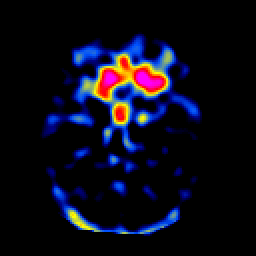

SPECT TL Study #3 -- Slice #19

[Home][Help][Clinical][Tour 1][Tour 2][Tour 3] Slice 19